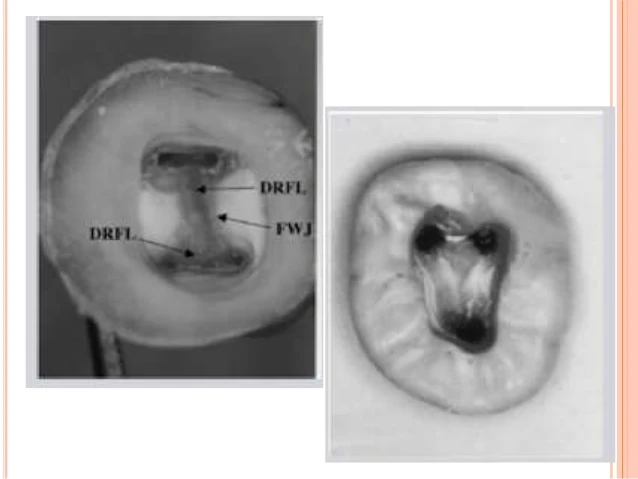

QUY LUẬT VỊ TRÍ LỖ TỦY

Quy luật 1: “Lỗ tủy chân răng luôn luôn nằm trên đường nối sàn – thành buồng tủy”.

Quy luật 2: “Lỗ tủy chân răng nằm tại đỉnh của đường nối sàn – thành buồng tủy”. Các quy luật đối xứng và vị trí lỗ tủy cho phép ta xác định được chính xác vị trí và số lượng lỗ tủy chân răng cần tìm.

Nguồn: Krasner P, Rankow HJ: Anatomy of the pulp chamber floor. J Endod 30(1):5, 2004.